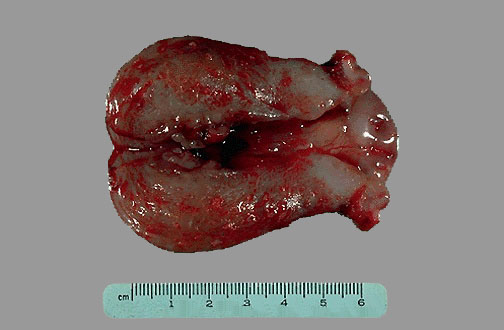

Este útero es de tamaño normal pero muestra una masa irregular en la parte superior del fundus que mostró ser tumoral en la biosia